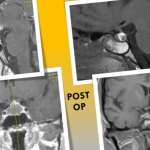

Таку операцію зробили лікарі нейрохірургічного відділення Херсонської обласної лікарні, повідомляється на сайті медзакладу: Попри те, що абсцес гіпофізу є досить